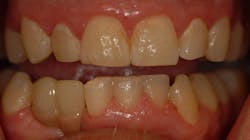

A full-thickness flap is reflected to visualize the bone and confirm positioning through the surgical guide. The guide is designed with windows to visualize proper seating. The surgical guide fully limits the implant drill in all dimensions, including depth, making it possible to drill to the final osteotomy depth and width with one drill. The implant fixture was placed and allowed to heal for four months with a healing abutment. The presurgically planned prosthesis was lab fabricated and delivered (figures 6 and 7).

The patient was pleased with the final result. A CBCT scan allowed this difficult surgical and esthetic case to be planned thoroughly beforehand. 3-D printing economically realized the planning in the actual surgery and prosthesis. 3-D printing in surgical guide fabrication allowed for more efficient and precise implant placement and restoration (figures 8 and 9).